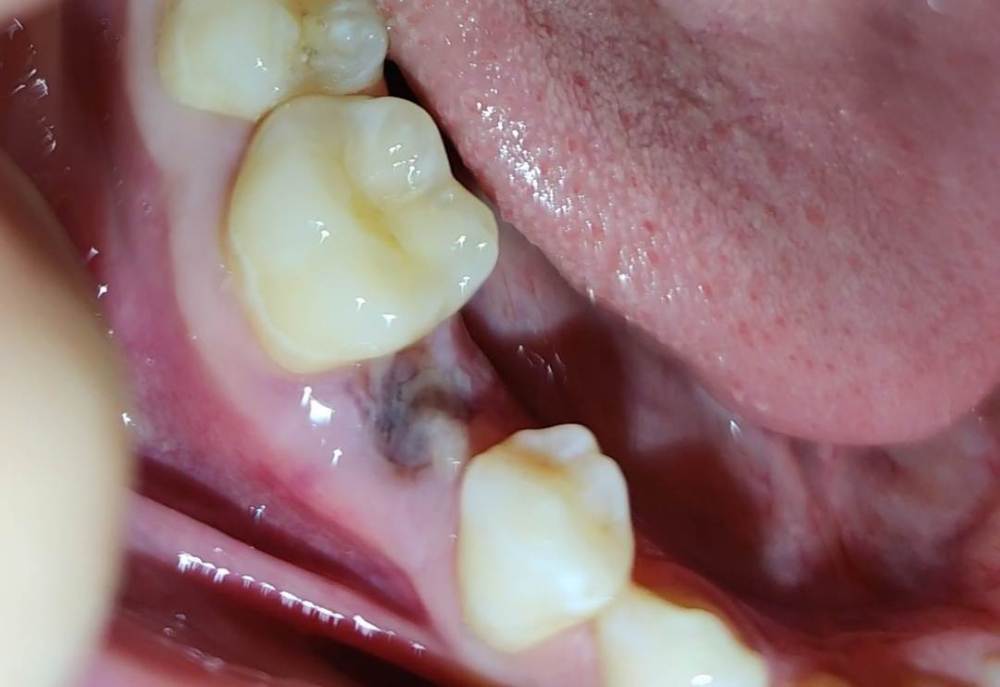

sunheaZ Опубликовано 9 декабря, 2022 Поделиться Опубликовано 9 декабря, 2022 (изменено) Добрый вечер! После удаления прошло полтора дня. Сегодня появился бугорок, это норма или я что-то сделал не так? Скрытый текст Скрытый текст Скрытый текст Скрытый текст Боли нет, но немного переживаю насчет нормальности восстановления Изменено 9 декабря, 2022 пользователем sunheaZ Ссылка на комментарий

Женька Опубликовано 9 декабря, 2022 Поделиться Опубликовано 9 декабря, 2022 Здравствуйте. С лункой всё хорошо. Если нет признаков воспаления (боль, отёк, гиперемия (покраснение), повышение температуры) то беспокоиться не стоит. Мой Вам совет, лишний раз не смотрите и не проверяйте, как у там дела 2 1 Ссылка на комментарий